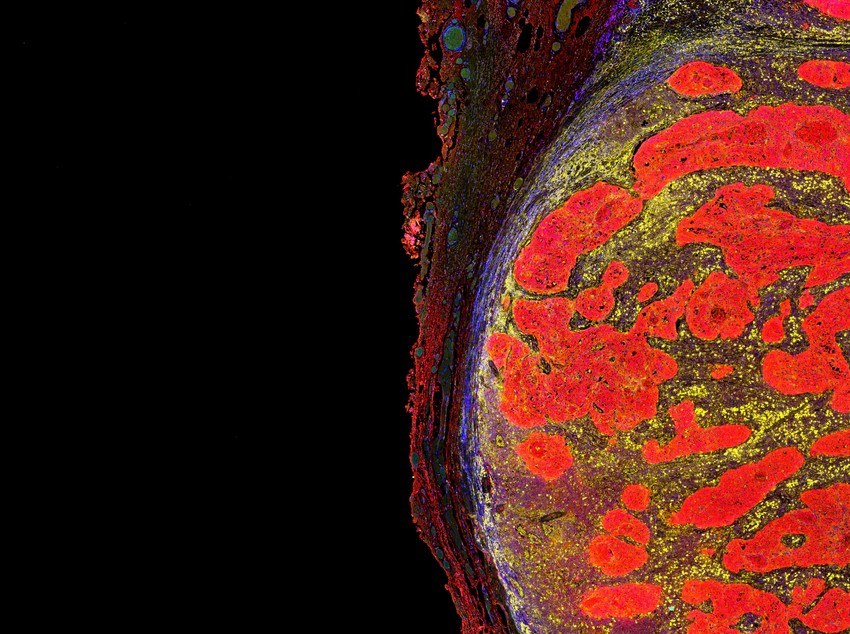

A kutatók megfigyelték, hogy a csernobili farkasok immunrendszere másnak tűnik, mint a normál farkasoké. Olyan génmutációkat fedeztek fel, amelyek ellenállóbbá teszi az állatokat a rákkal szembeni. Ez a felfdezés fontos lehet az emberi rákkutatás szempontjából is, hiszen segíthet megérteni, hogyan lehetnek bizonyos génmutációk előnyösek a rák túlélésében.

Love azonosította a farkasok genomjának specifikus régióit, amelyek ellenállónak tűnnek a rákkal szemben, ám a kutatócsoport egyelőre nem tud visszatérni a csernobili zárt övezetbe a világjárvány és a politikai helyzet miatt, de munkájuk folytatása fontos lenne további információk begyűjtése érdekében.

Hideg és forró tumorok: ettől függhet az immunterápiás rákkezelés hatásossága!